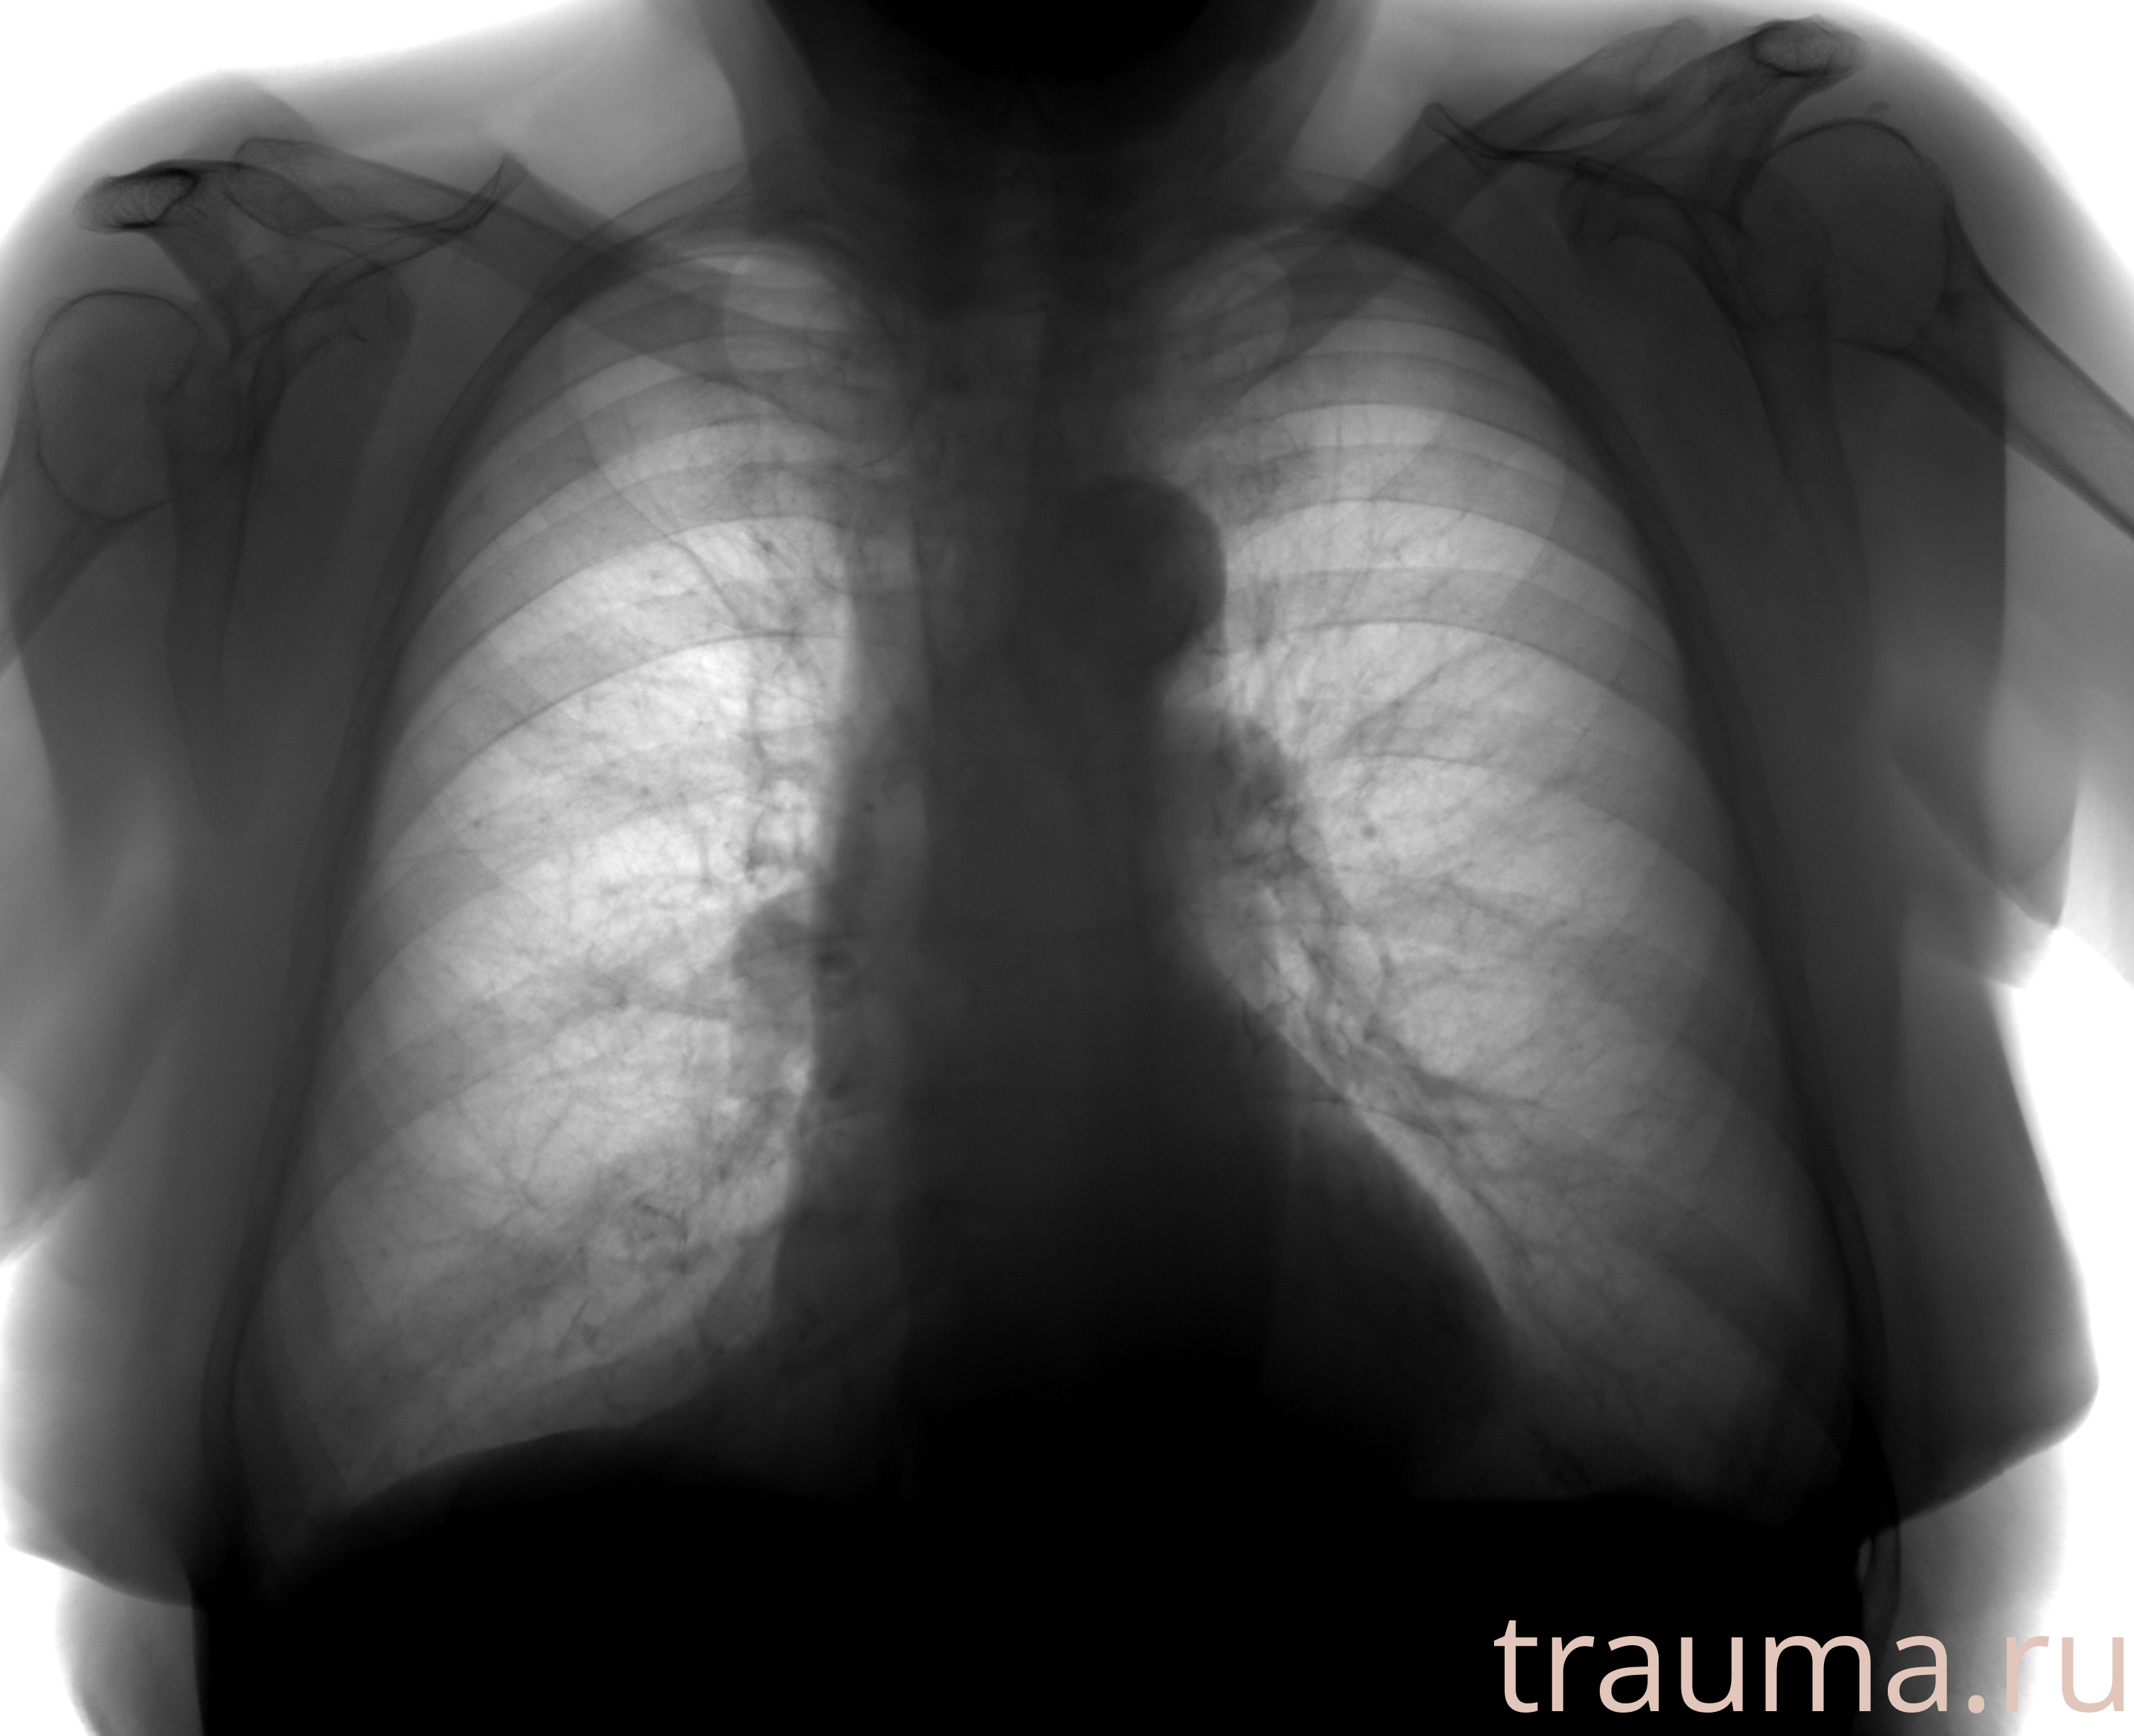

Рентгенограммы

Рентген на дому: по вашему адресу приезжает врач-рентгенолог, травматолог-ортопед с мобильным рентгеновским аппаратом, проводит диагностику травмы или заболевания, делает необходимые рентгенограммы, дает рекомендации по дальнейшему лечению. Получить качественные снимки в домашних условиях возможно благодаря уникальной методике, разработанной МосРентген Центром для института  Склифосовского

при переломе шейки бедра и пневмонии от компании МосРентген Центр - партнера Института имени Склифосовского